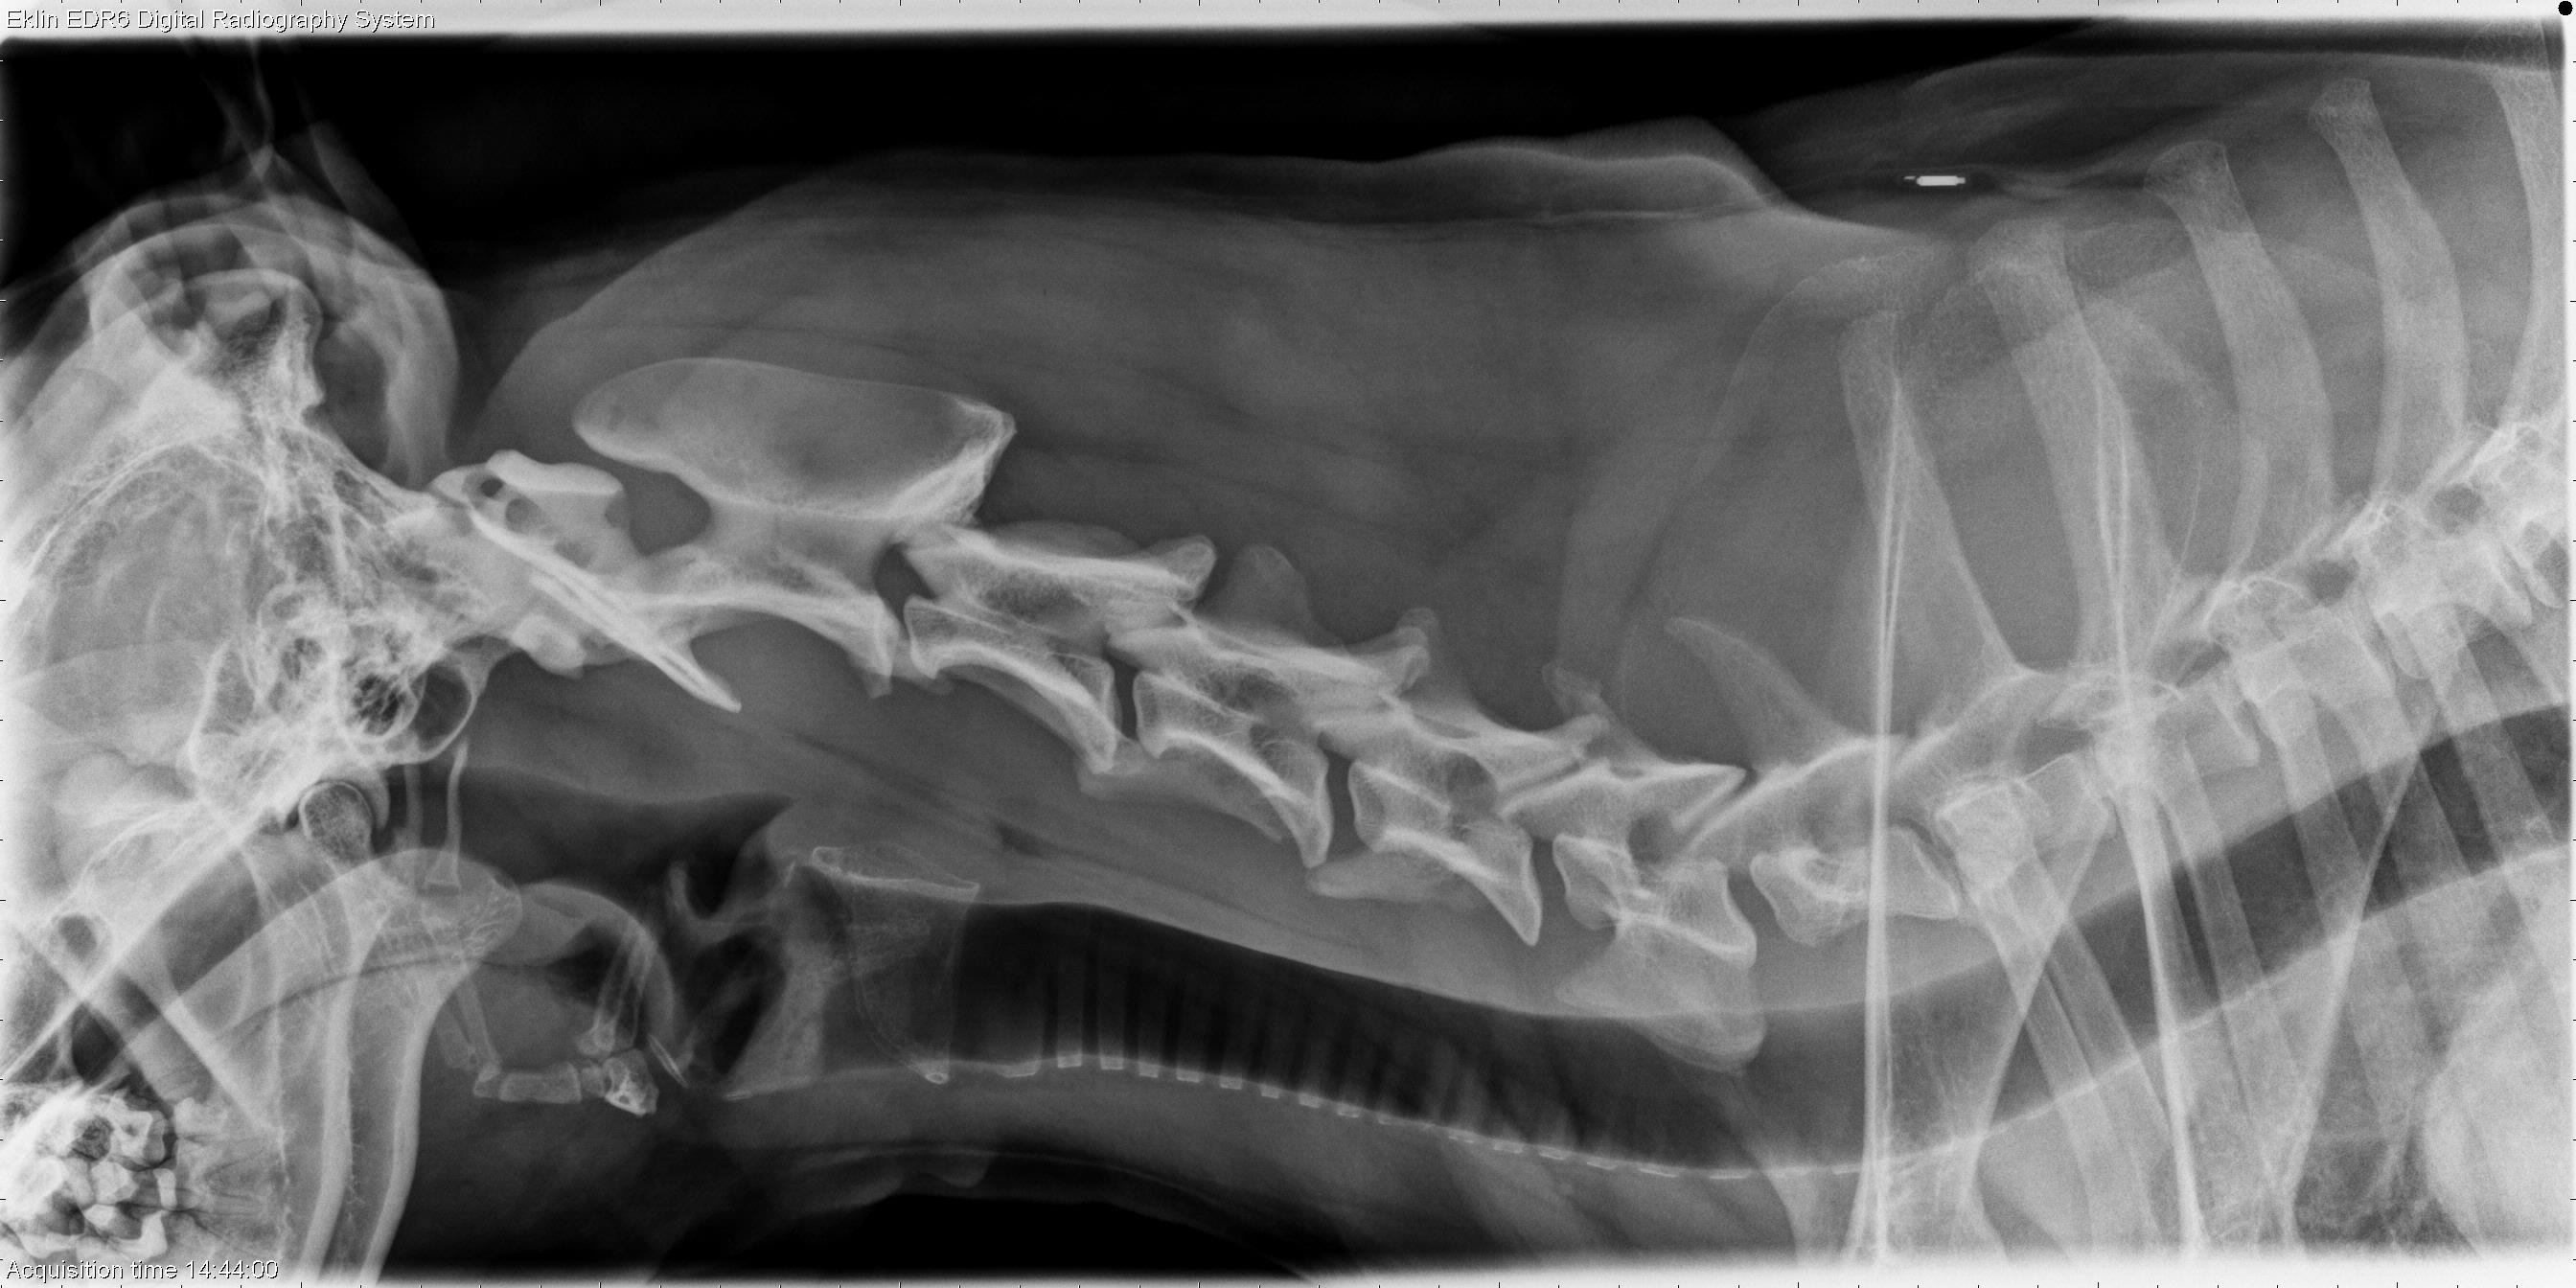

3 year old German Shepherd

Today’s case is a 3 -year-old female neutered German Shepherd dog with lameness and pain in the pelvic region. Progression to ataxia. Once you have decided whether the lesion is aggressive or not, prioritize your differential diagnoses.

R LAT Spine

On lateral projections of the spine, there are multifocal areas of lysis centered on intervertebral disc spaces (T10-11, T13-L1, L4-5, L6-7). There is sclerosis of the vertebral bodies surrounding the lytic lesions. Varying degrees of spondylosis deformans are present ventrally.

• Multifocal discospondylitis secondary to Aspergillus infection. Serum and urine were antigen positive, and fungal hyphae were seen on histopathologic sections.